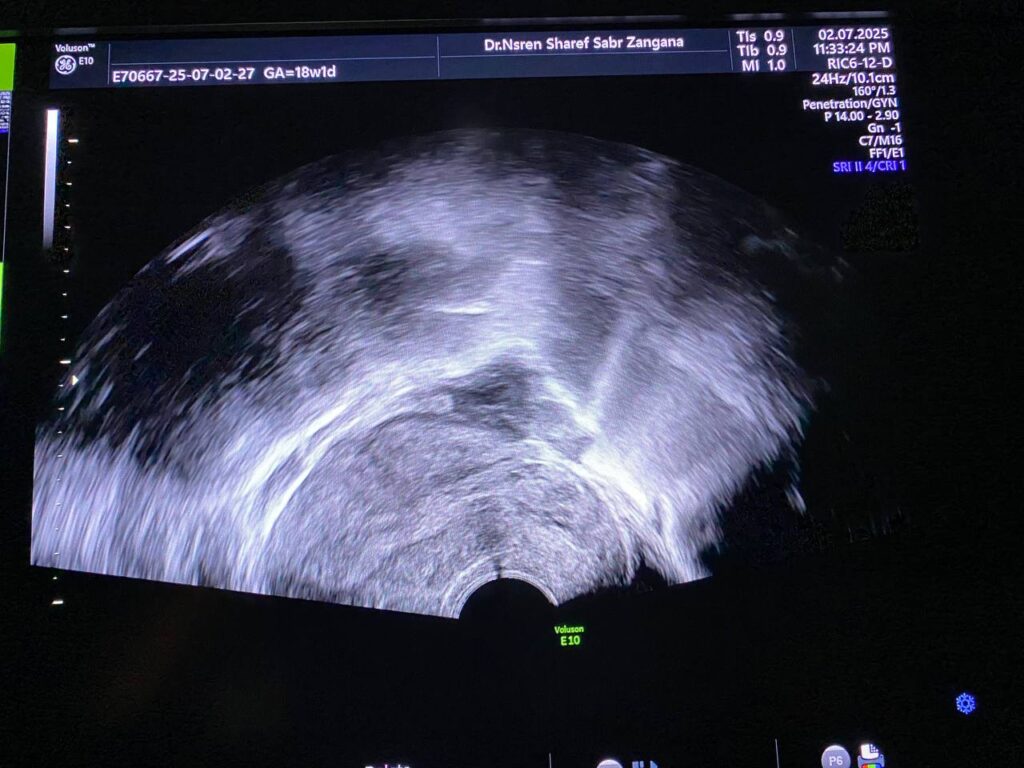

Bulky size, R/V uterus, endometrial lining thickness 13mm, with presence of isoechoic mass 36x12mm , within the cavity and nearly at level of interval os , incomplete abortion ? submucosal fibroid ? please for further study ill-defined endo-myometrial junctional zone, hypertrophy & asymmetry of the junctional myometrial layer, with presence few small cystic within the junctional layer, picture mostly of adenomyosis changes